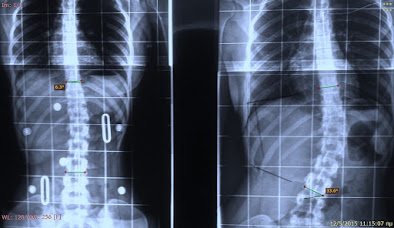

Watching Elise Browning Miller’s recent interview with Christine Jaureguiberry (on Christine’s Yoga for Scoliosis Community Youtube channel), I was particularly interested in their discussion about adult onset scoliosis. Teen years and puberty tend to be the main focus for when scoliosis develops, but as scoliosis is more prevalent in women than in men (8:1), there is evidence that periods of major hormonal fluctuation (childbirth and menopause) can trigger a later change in spinal structure. Age can contribute, with degenerative discs, softening of tissues, and arthritis, so that an adult can develop a curve that they previously did not have at all. But it’s also possible to have a mild, idiopathic scoliosis that remains nearly undetectable throughout life, which then increases after menopause.

For individuals diagnosed with a spinal curve, it’s common to feel pain in a hip or leg, or in your back, and this is often the reason a diagnosis is sought out. Elise talks about the importance of developing a regular (daily) practice that addresses the specific curve(s). She recommends starting off simply, maybe just figuring out a few poses that work and getting into a regular routine of body focus while doing this practice. In her book Yoga for Scoliosis – A Path for Students and Teachers, she offers many options for creating a routine as well as a more complex dive into the specifics of an individual’s own curve pattern, or “body map,” and ideas for addressing each one.

If you are dealing with mysterious chronic pain in a hip or leg, or in your back, you might mention it to your doctor, who could rule out a developing curve. The wonderful thing about Elise’s teaching and her book is that building body awareness is key to optimal functioning, whether you have a curve or not, so following her direction on tuning into your body is a good plan for everyone!